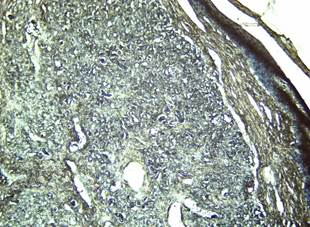

Figura 5. Marcada proliferación dérmica de colágenos desorganizados, con escasa presencia de tejido conjuntivo difuso. Coloración Tricrómico de VanGieson 4 X.

Elaboración: Los autores.

Durante la segunda etapa de la técnica histoquímica donde se lava la muestra y se aplica fucsina ácida y ácido pícrico saturado, se observan numerosos fibroblastos con núcleos azules (Figura 5), mientras que las fibras colágenas toman una tonalidad gris o negra. Se observa proliferación de fibras elásticas coloreadas también de negro pero más delgadas que las colágenas. En esta figura se observa que las fibras colágenas predominan en la periferia de la lesión, mientras las elásticas se concentran alrededor de los vasos sanguíneos, típico de los fibrohemangiomas. La gran proliferación de fibroblastos indica la reactividad del tejido conjuntivo ante la presencia de un agente etiológico, lo cual conduce a la intensa proliferación de colágeno e instaurándose en la dermis escrotal un proceso fibrótico. (Figura 5). Este resultado es compatible con lo reportado por Méndez Rodriguez et al. (2021).

Figura 6. Hiperqueratosis epidérmica y en la dermis se observan numerosos fibroblastos (núcleos azules), fibras colágenas, más abundantes hacia la periferia de la lesión, y fibras elásticas (más delgadas), alrededor de los vasos sanguíneos, todas con tonalidad gris o negra. ColoraciónTricrómico de Van Gieson 4 X.